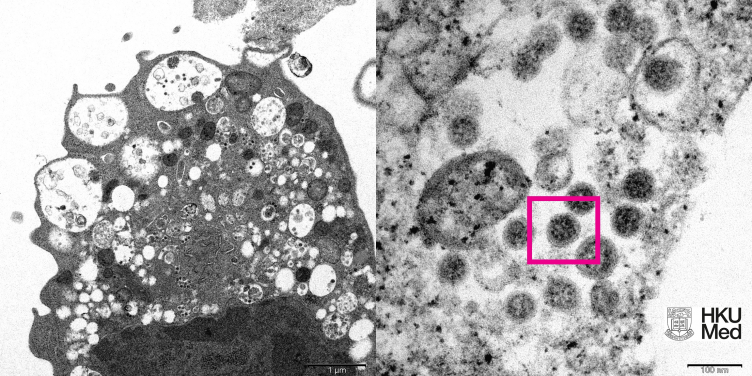

左圖:低倍電子顯微鏡下感染新型冠狀病毒 Omicron 變異株 24 小時後的猴腎細胞(Vero)。方框內顯示細胞質中的病毒顆粒聚集體。

中圖:高倍電子顯微照片顯示,左圖大方框內囊泡裡的病毒顆粒聚集體和細胞表面上的病毒顆粒。

右圖:左圖小方框內擁有刺狀的病毒顆粒經高倍電子顯微鏡放大後的影像。

圖片由香港大學李嘉誠醫學院(港大醫學院)病理學系臨床教授黎國思教授、公共衞生學院譚華正基金教授(醫療科學)兼病毒學講座教授裴偉士教授、公共衞生學院教授及公共衞生實驗室科學分部主任潘烈文教授,及香港大學電子顯微鏡研究所提供。